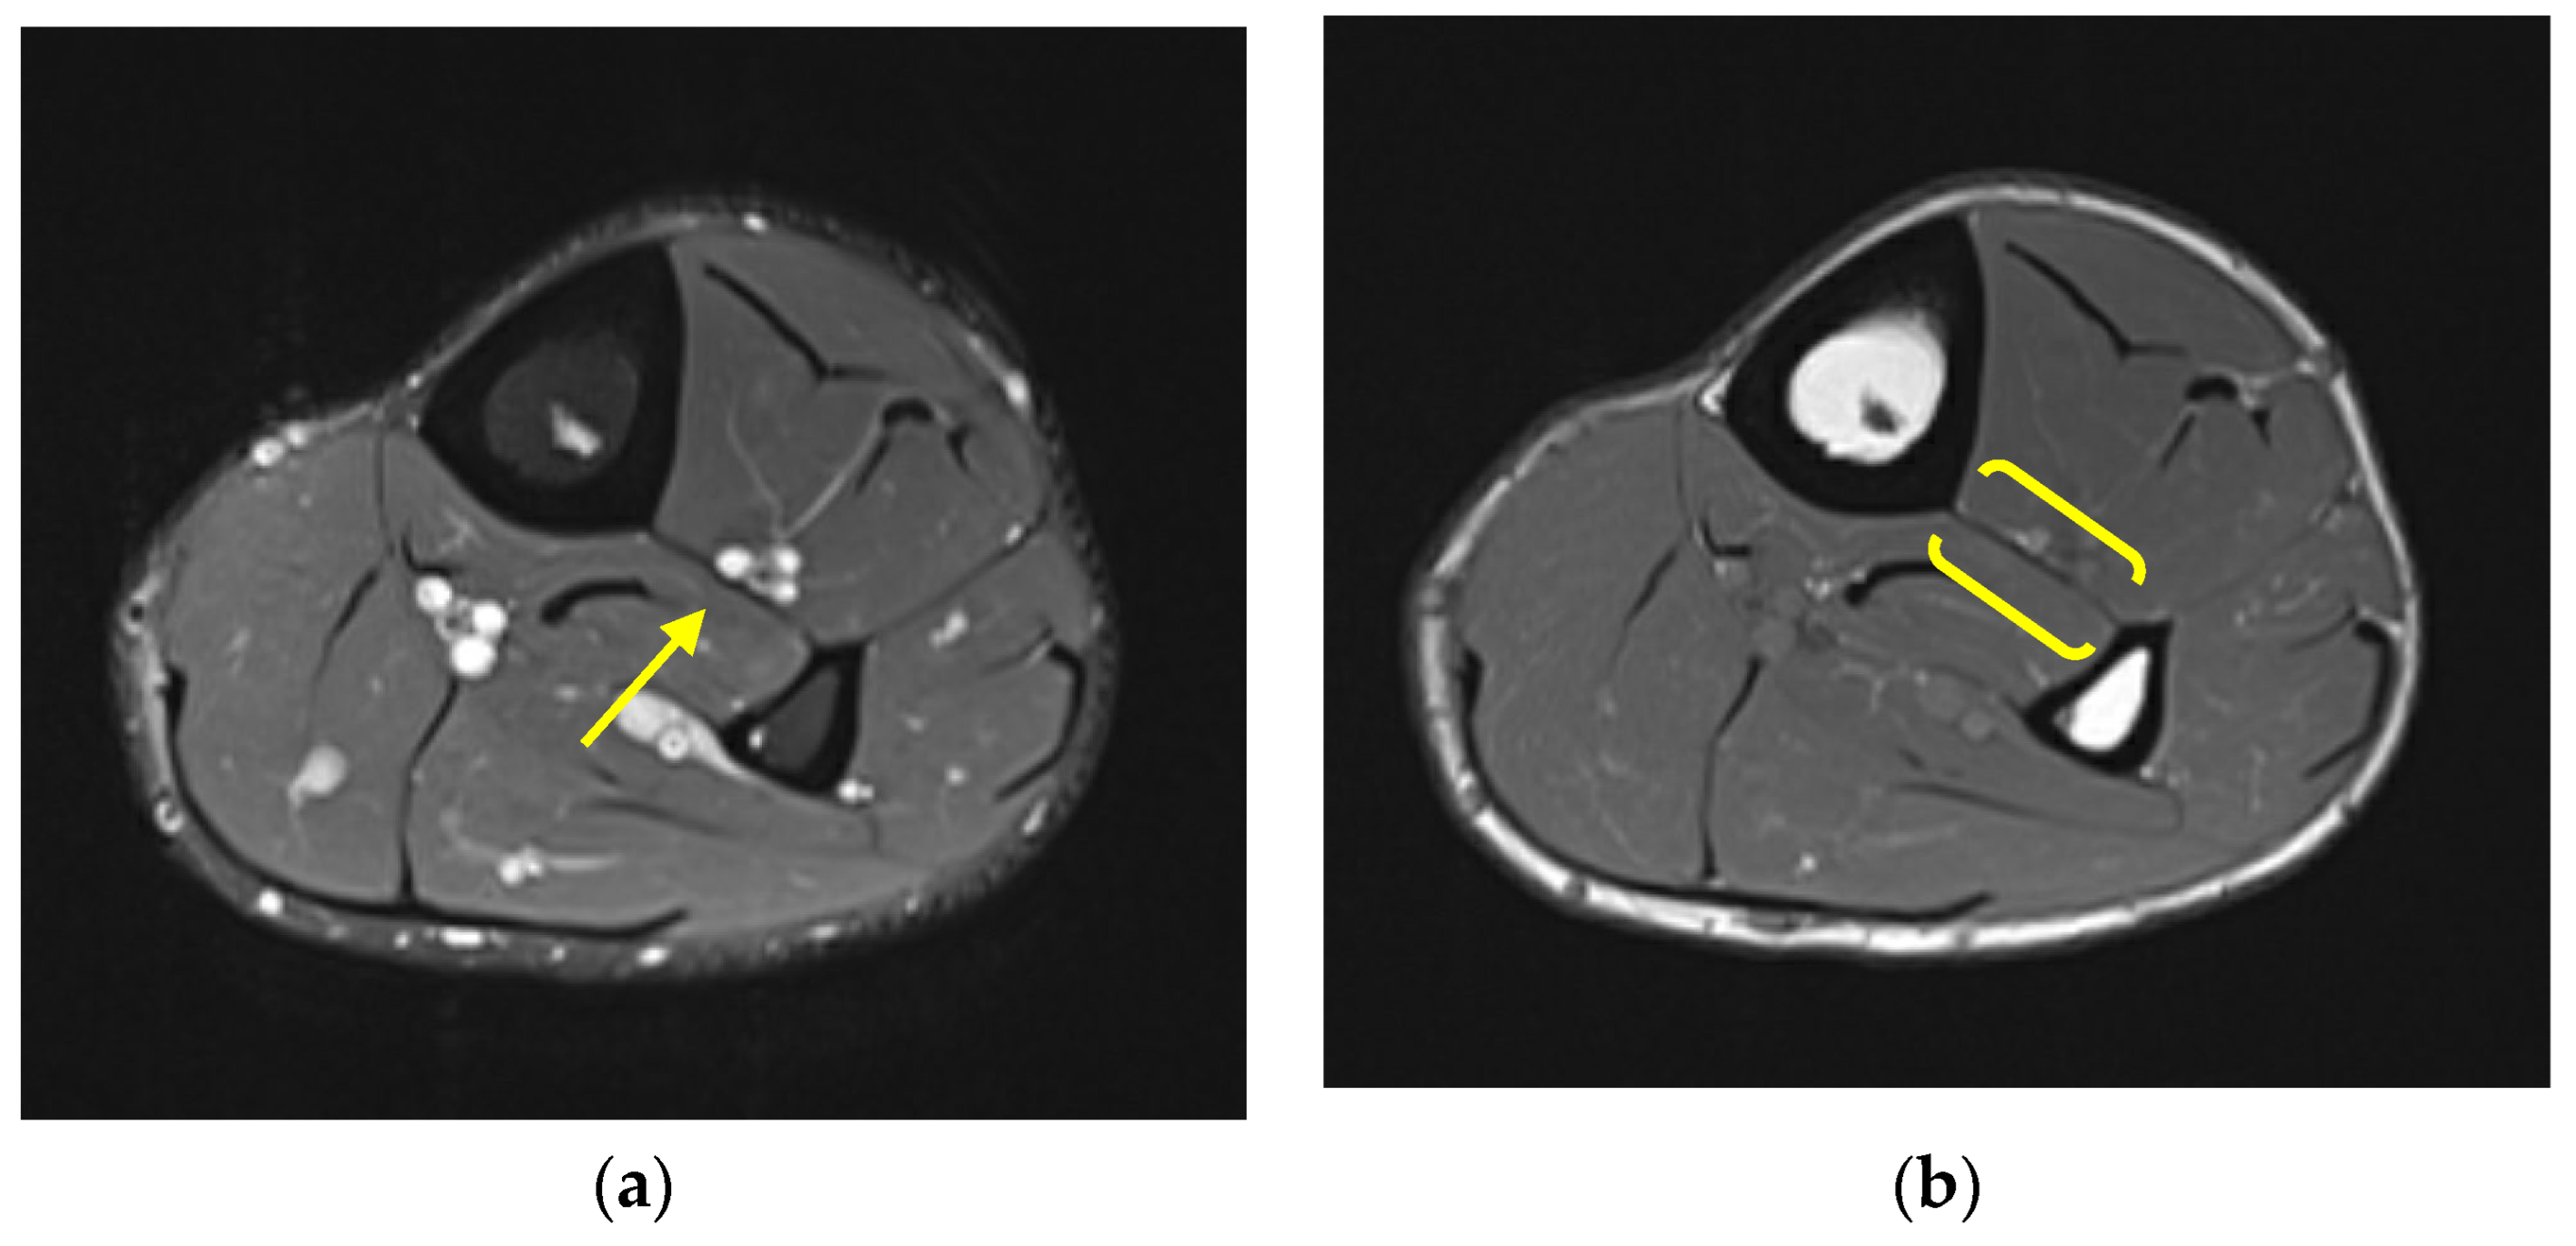

The IOM can be evaluated by a variety of modalities including ultrasound, CT, and MRI. On all modalities, a normal IOM appears as a thin and continuous membranous structure extending between the tibia and fibula. On MRI, the normal IOM is thin and hypointense in all sequences and extends from the proximal tibiofibular joint to the distal tibiofibular syndesmosis (Figure 4). The anterior tibialis and posterior tibialis muscles have broad attachments on the anterior and posterior aspects of the IOM, respectively.

Figure 4. Normal comparison. (a) Axial proton density fat saturated MR image and (b) axial T1-weighted MR image demonstrate a normal MRI appearance of an intact IOM (yellow arrow and brackets) at the level of the mid tibia–fibula.